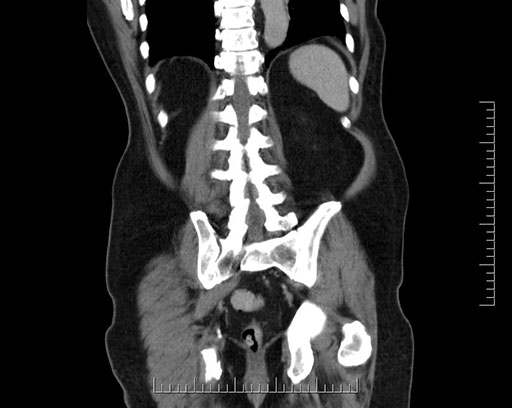

Coronal - stented